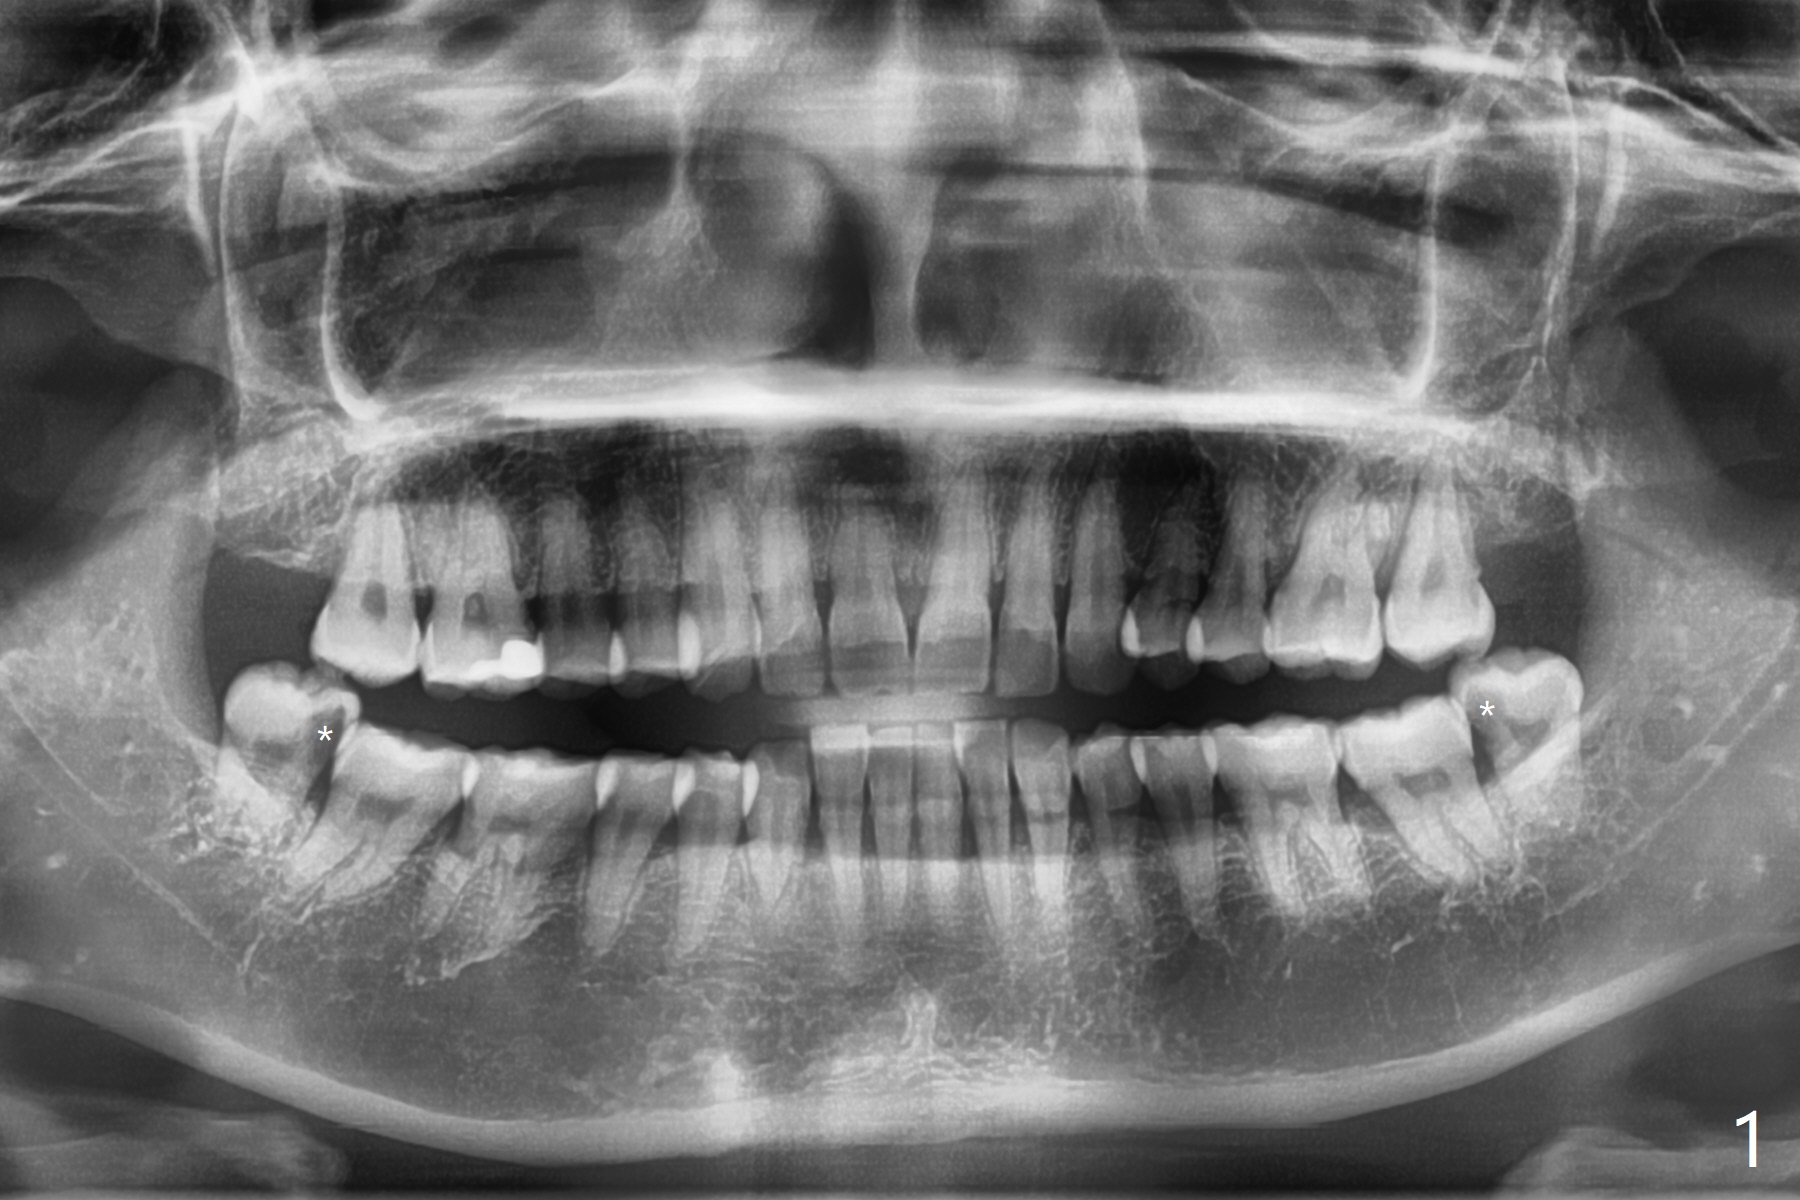

48岁女,害怕牙科,左下冷热敏感,夜间痛,下颌智齿过度萌出,颊侧近中龋齿(图一:*),需要深洗。左下智齿拔除顺利。